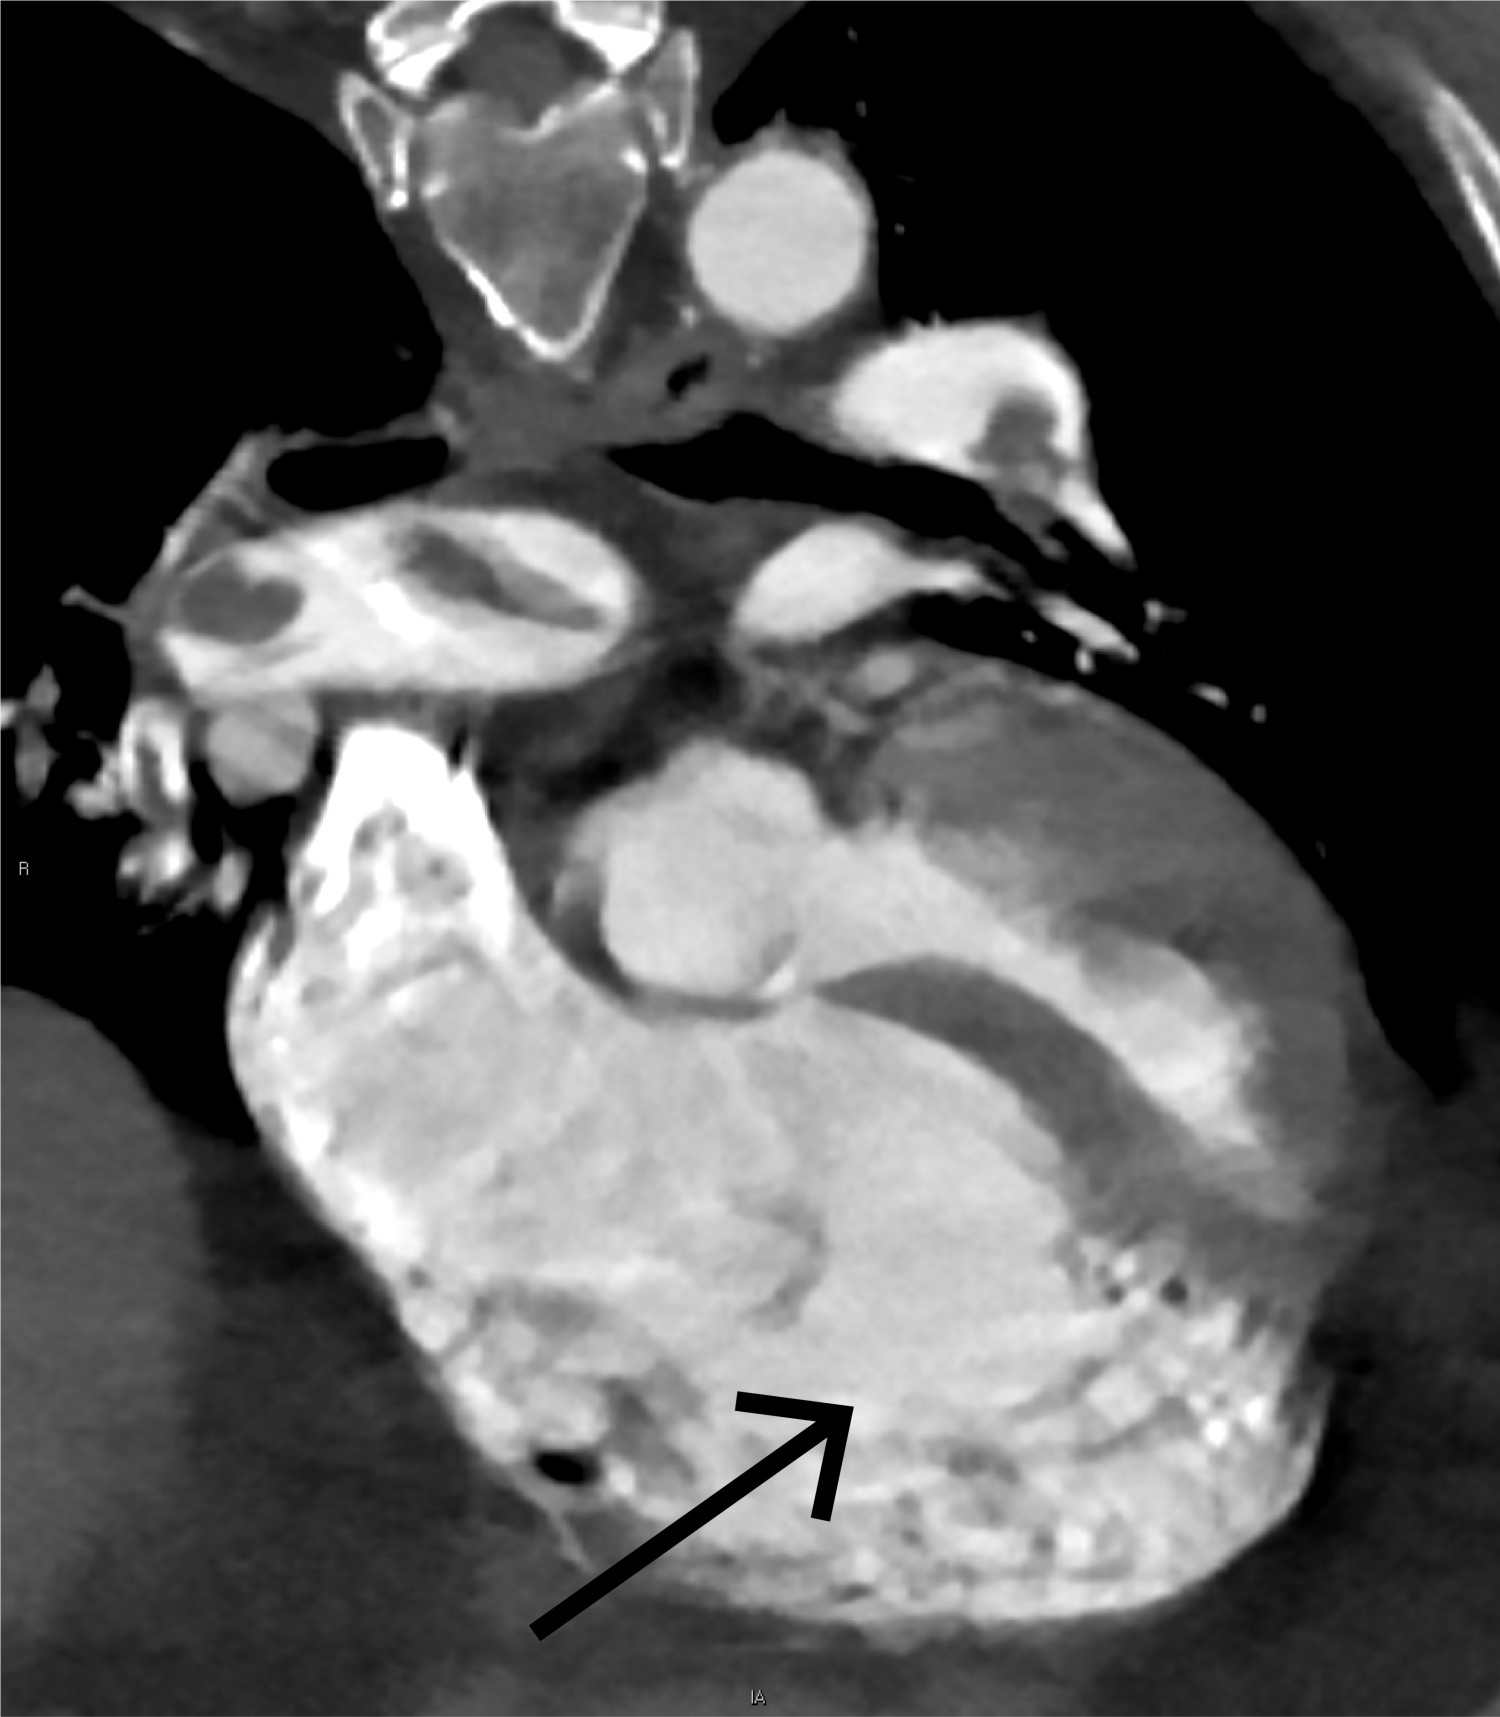

CT toraks med lungeemboliprotokoll viste sadelemboli, med tromber ut i de fleste større lungearterier og med affeksjon av alle lungelapper på lobært og segmentalt nivå (figur 4 og 5). Størst utfall var i underlapper. Aortadisseksjon ble ikke påvist.